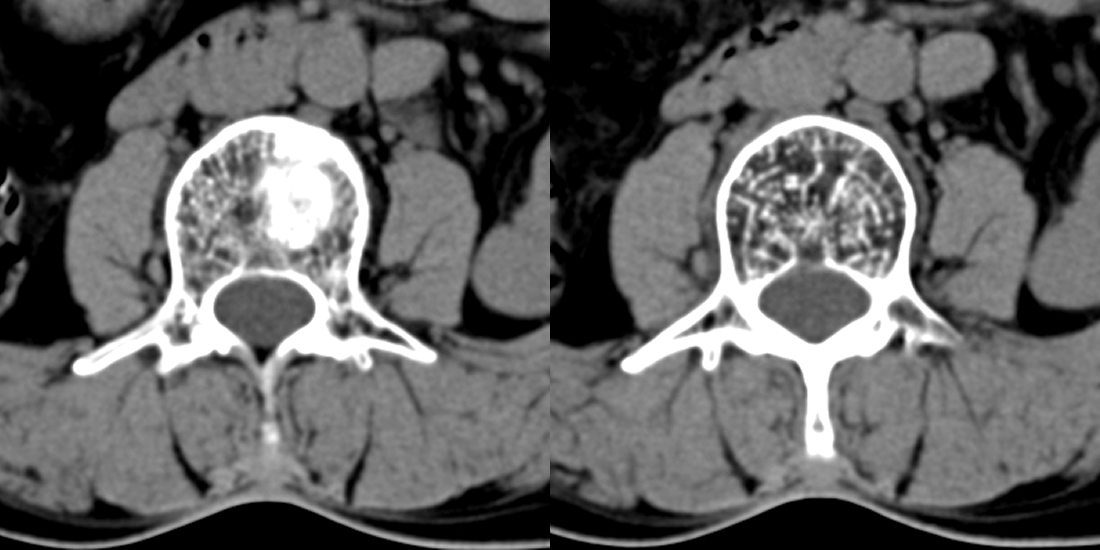

1、腰3椎体斯莫氏结节;

2、腰椎骨质增生。

1、腰3椎体斯莫氏结节;2、腰椎骨质增生。